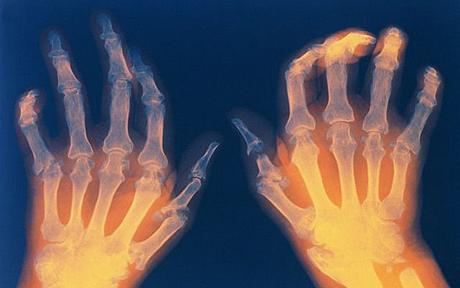

รูมาตอยด์ โรคข้ออักเสบตัวร้าย ใช่..ขึ้นหัวข้อแบบนี้แหละ ลองนึกดู คุณเคยยกของหนักมากๆจนปวดหลังประมาณว่านอนแล้วลุกขึ้้นไม่ไหว มีใช่ไหมคะ ความรู้สึกทรมานนั้นคุณจำได้ แต่อาการของคุณเป็นแค่ชั่วคราววันสองวันก็หาย สำหรับผู้ป่วยโรคข้ออักเสบรูมาตอยด์เจ้าตัวร้ายนี้ ทำให้เขาปวดทรมานตลอดชีวิต ทำความรู้จักเจ้าตัวร้ายกันก่อน โรครูมาตอยด์ เป็นโรคข้ออักเสบเรื้อรังที่เกิดจากความผิดปกติของระบบภูิมิคุ้มกันของร่างกายที่หลั่งสารออกมาทำลายเยื้อบุข้อ เป็นผลทำให้เยื้อบุข้ออักเสบหนาตัวขึ้น สร้างน้ำไขข้อเพิ่มขึ้น สังเกตเ...